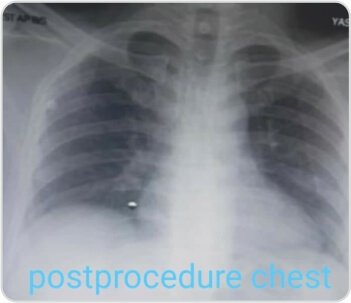

التصوير الشعاعي للصدر بعد الإجراء